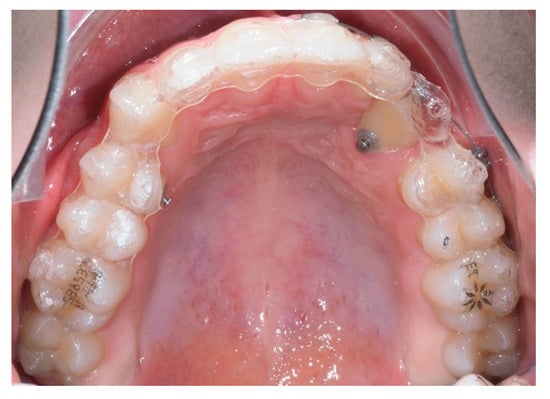

Approximately 7 months later, a palatal mini-implant was placed between teeth 24 and 25, serving as stable anchorage for distal traction using an elastic chain, which was replaced monthly (Figure 15). This movement positioned the canine away from the lateral incisor root. Aligners were customized and adjusted throughout treatment.

Figure 15.

Adjusted aligners, palatal mini-implant, and elastic chain used for distalizing the canine; 7 months after the surgery.